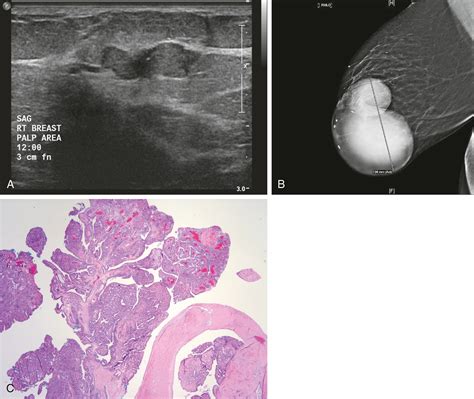

An intraductal papilloma is a small, benign growth that develops inside a milk duct. It is composed of glandular tissue, fibrous tissue, and blood vessels. These growths can occur anywhere along the ductal system, though they are frequently found near the nipple. They are most commonly diagnosed in women between the ages of 35 and 55.

Because clinical examination alone cannot definitively distinguish a benign papilloma from other breast conditions, including breast cancer, imaging and diagnostic procedures are required. A breast specialist will typically follow a systematic approach to diagnosis:

Breast Ultrasound High-resolution imaging used to evaluate lumps and look inside the ducts for abnormal growth.

Ductogram (Galactogram) A specialized test where contrast dye is injected into the affected duct to visualize the blockage or growth.

Core Needle Biopsy Removing a small tissue sample for laboratory analysis to confirm the diagnosis definitively.

Following surgical removal, the tissue is sent to a pathologist for microscopic examination. In the vast majority of cases, these tumors are completely benign. However, if the pathology report indicates the presence of atypical hyperplasia (abnormal, but not cancerous cells) within the papilloma, the doctor may recommend closer monitoring or further treatment, as this may slightly increase the long-term risk of breast cancer.